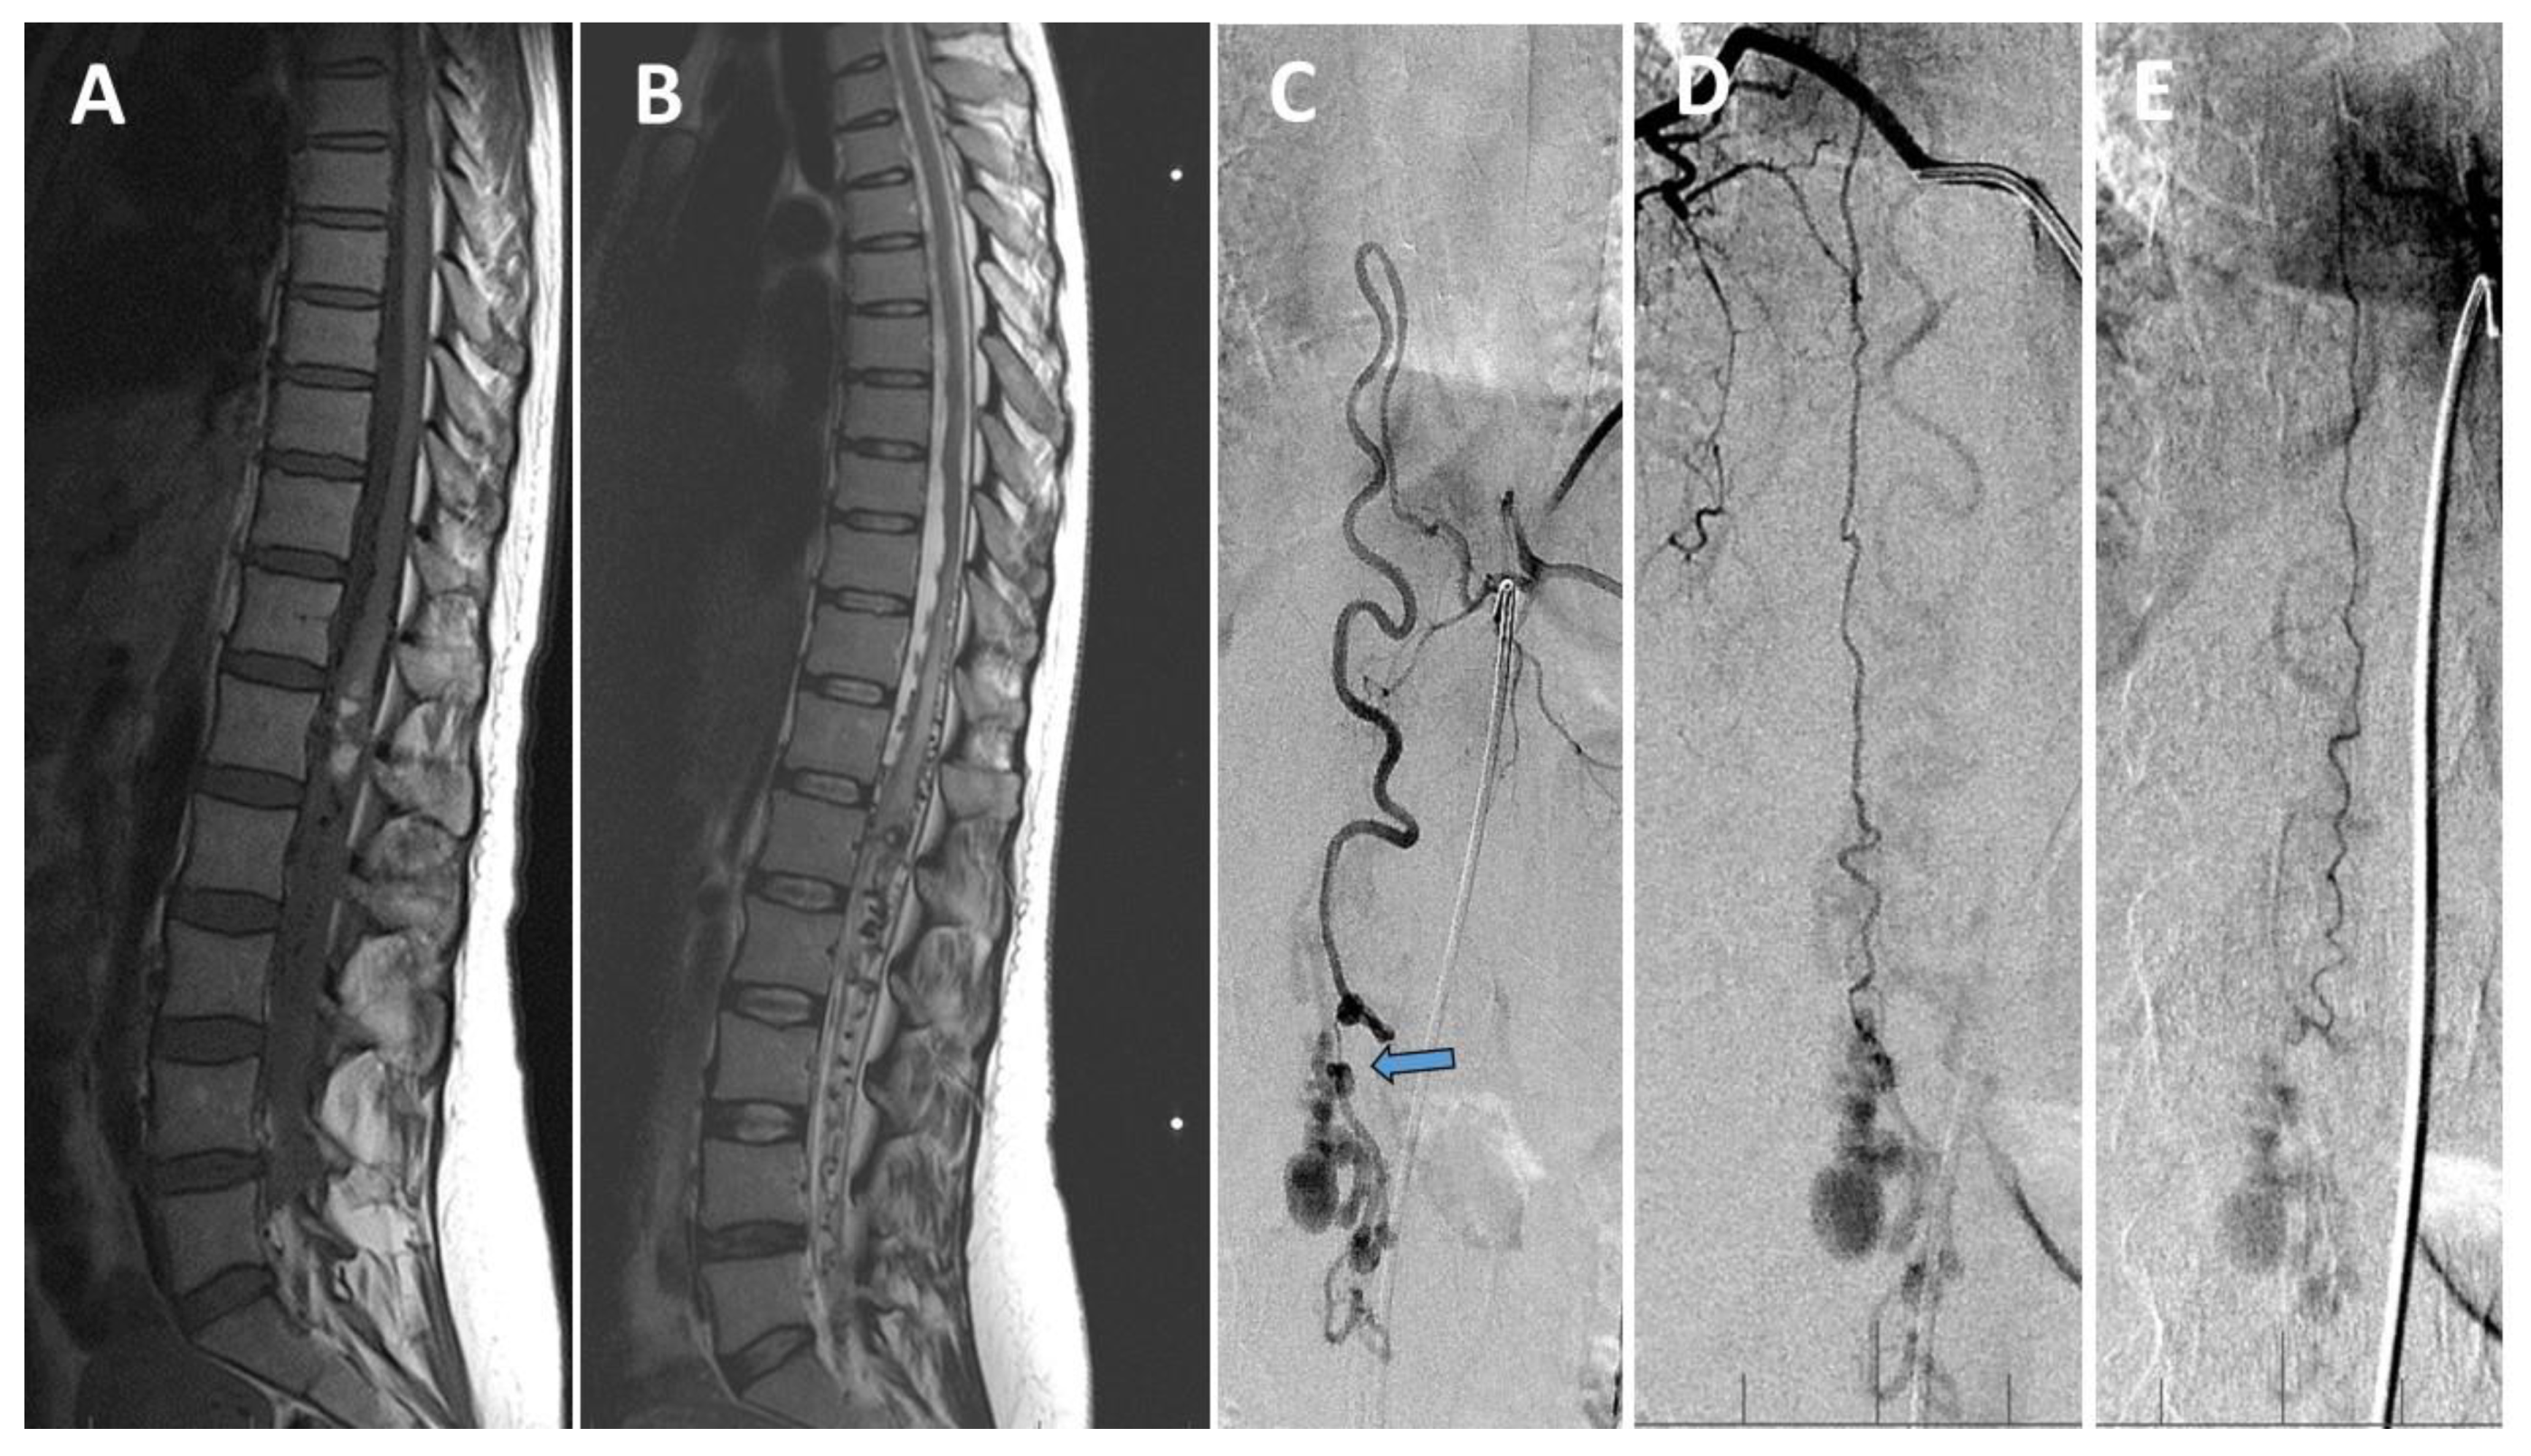

2. Case Report